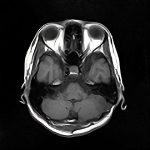

脳腫瘍 手術実績

症例 '16年11月

No.

※ 画像をクリックすると拡大表示します。症例No.は平成29年から起算しています。

年_番号

手術年月

患者年齢

’16_169

'16年11月

40代

病名

術式

備考

海綿状血管腫

断層撮影

手術前

1

手術前2

手術後